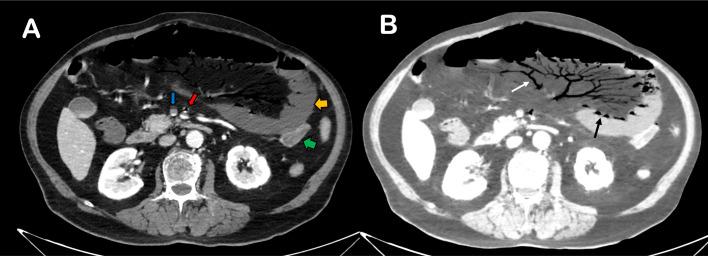

Contrast-enhanced abdominal CT is the gold standard for the diagnosis of acute mesenteric ischemia (AMI). CT findings include several anomalies like bowel wall thickening, thinning, attenuation, decreased enhancement, dilated fluid-filled loops, pneumatosis, and portal venous gas. A rare case of gas found only in the superior mesenteric artery (SMA) is presented. A contrast-enhanced CT scan was performed in emergency on an 80-year-old man with vague and diffuse abdominal pain, which showed findings of occlusive AMI. Gas was found in the context of the SMA and its branches, but not in the mesenteric and portal veins. The patient underwent emergency surgery but he died the next day in the intensive care unit for complications. The rare CT finding of gas in SMA during an AMI should be considered a radiological sign of irreversible intestinal damage: surgical prompt intervention is needed, even if the mortality rate is high.

腹部增强CT是诊断急性肠系膜缺血(AMI)的金标准。CT表现包括多种异常,如肠壁增厚、变薄、密度减低、强化减弱、扩张的充满液体的肠袢、积气以及门静脉积气。本文报告了一例仅在上肠系膜动脉(SMA)发现气体的罕见病例。一名80岁男性因腹部模糊性弥漫性疼痛在急诊时进行了腹部增强CT扫描,结果显示为闭塞性AMI。气体出现在SMA及其分支内,但肠系膜静脉和门静脉内未发现气体。患者接受了急诊手术,但次日在重症监护病房因并发症死亡。AMI期间SMA内出现气体这一罕见的CT表现应被视为肠道不可逆损伤的影像学征象:即使死亡率很高,也需要迅速进行手术干预。